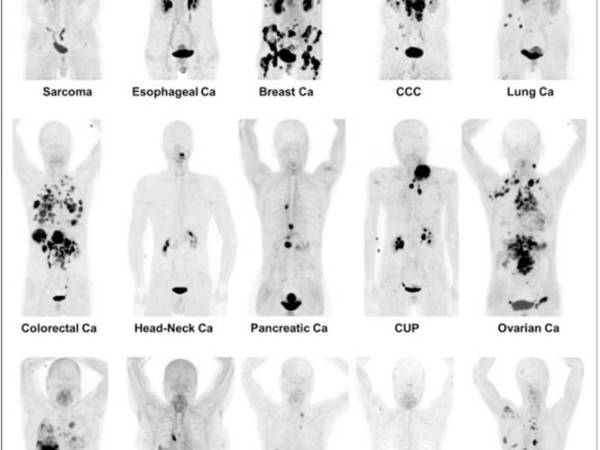

核醫診療學(Theranostics)是將診斷與治療結合的技術,核醫診療學的未來發展具有非常大的潛力,特別是在腫瘤學領域。